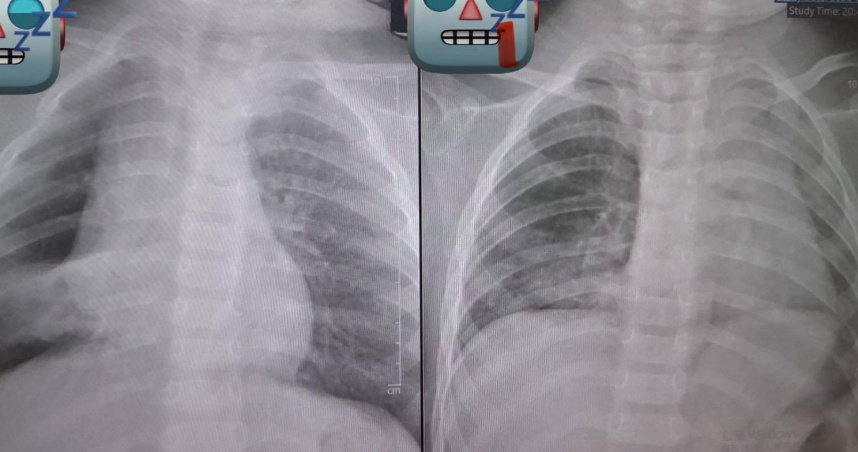

基隆長庚醫院兒科教授級主治醫師廖穗綾今(12)日在粉專發文指出,上週遇到一名緊急送來的1歲多幼童,據了解,孩子在3、4天前被阿嬤餵食了花生,隨後開始出現咳嗽與喘鳴聲,雖然剛開始症狀不明顯,但隔天追蹤X光發現,「肺部已經開始塌陷」,這絕非小事。

當晚該童轉入加護病房,廖醫師的丈夫賴醫師緊急召集加護病房團隊與資深技術員,準備透過支氣管鏡取出異物。然而,手術過程極度艱難,廖穗綾透露那顆花生已經卡了三天、肉芽長出來,「整顆又大又肥,死死塞住支氣管」;賴醫師更直言,他從來沒有遇過這麼困難的案例。